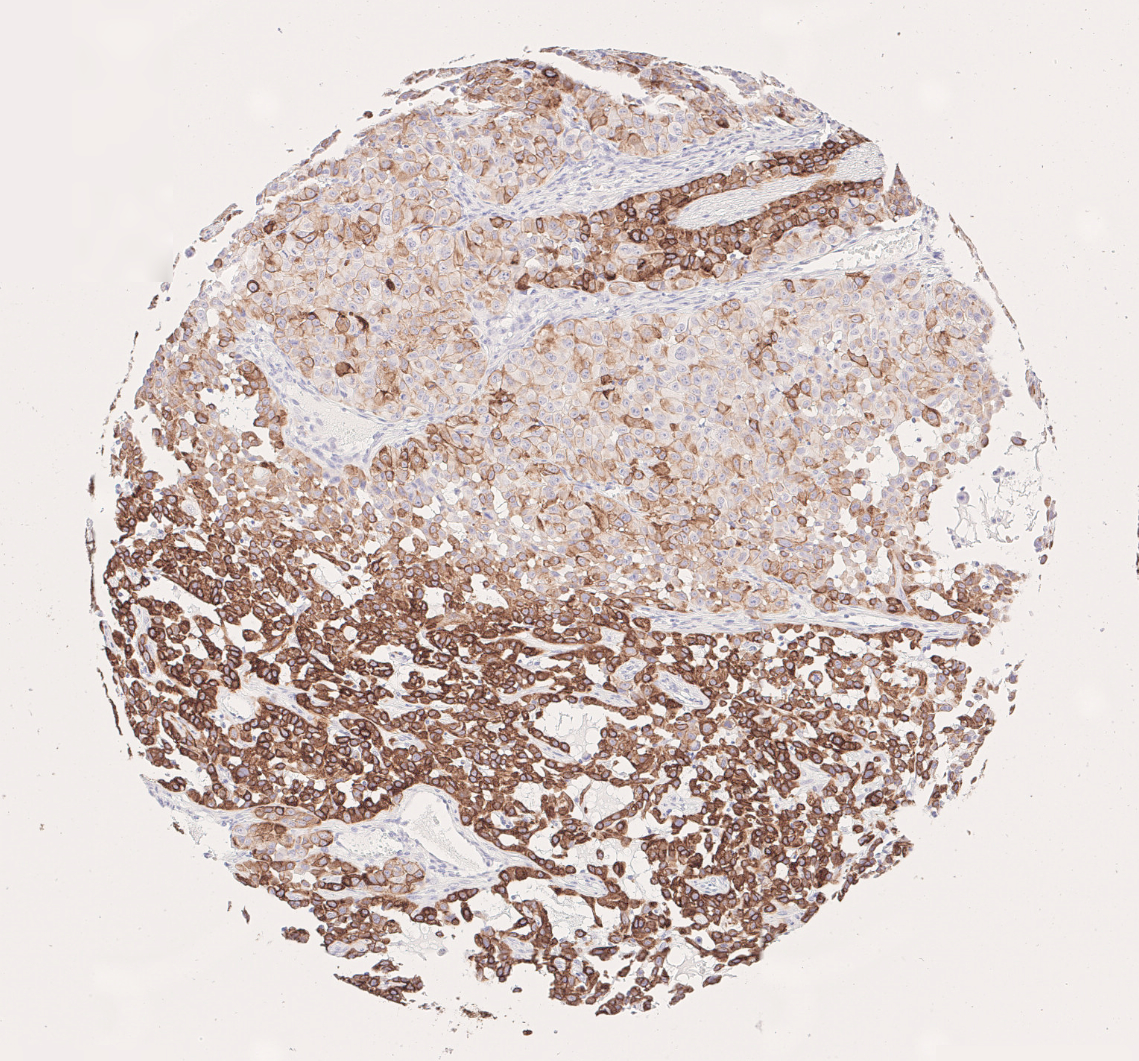

In summary, RNAseq scores and CK7 staining stores yielded comparable results in the present study. High RNAseq scores correlated with medium to high CK7 expression scores in IHC-P. In addition, CK7 expression analysis using immunohistochemistry visualizes tumor heterogeneity. This spatial information is lost in RNAseq. (Figure 6).

CK7 immunohistochemistry visualizes tumor heterogeneity in NSCLC adenocarcinoma subtype in a brownish color

Figure 6: CK7 immunohistochemistry visualizes tumor heterogeneity in NSCLC adenocarcinoma subtype.